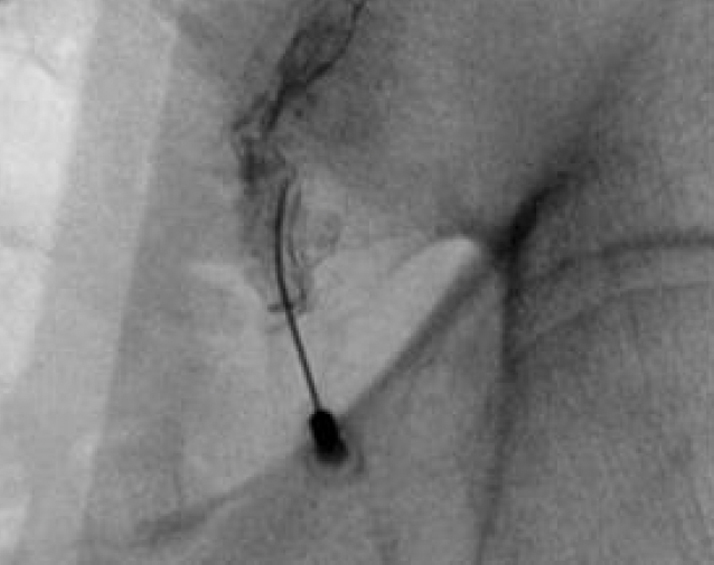

- Bi-lateral SI joint degeneration with pain post revision surgery verified via SI joint block injection.

- Bilateral SI joint fusion using the iFuse 3D™ Implant System, August 2020

Inline dennis 03